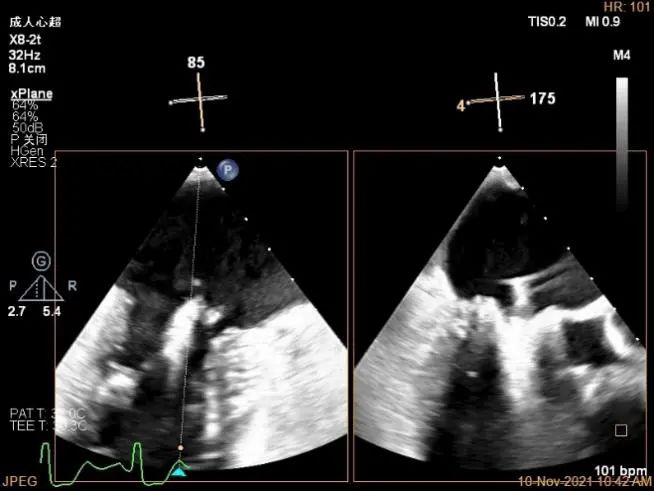

X-plane:下夹子尝试捕获2区脱垂瓣叶

3D证实夹子外侧残余脱垂及瓣叶裂空